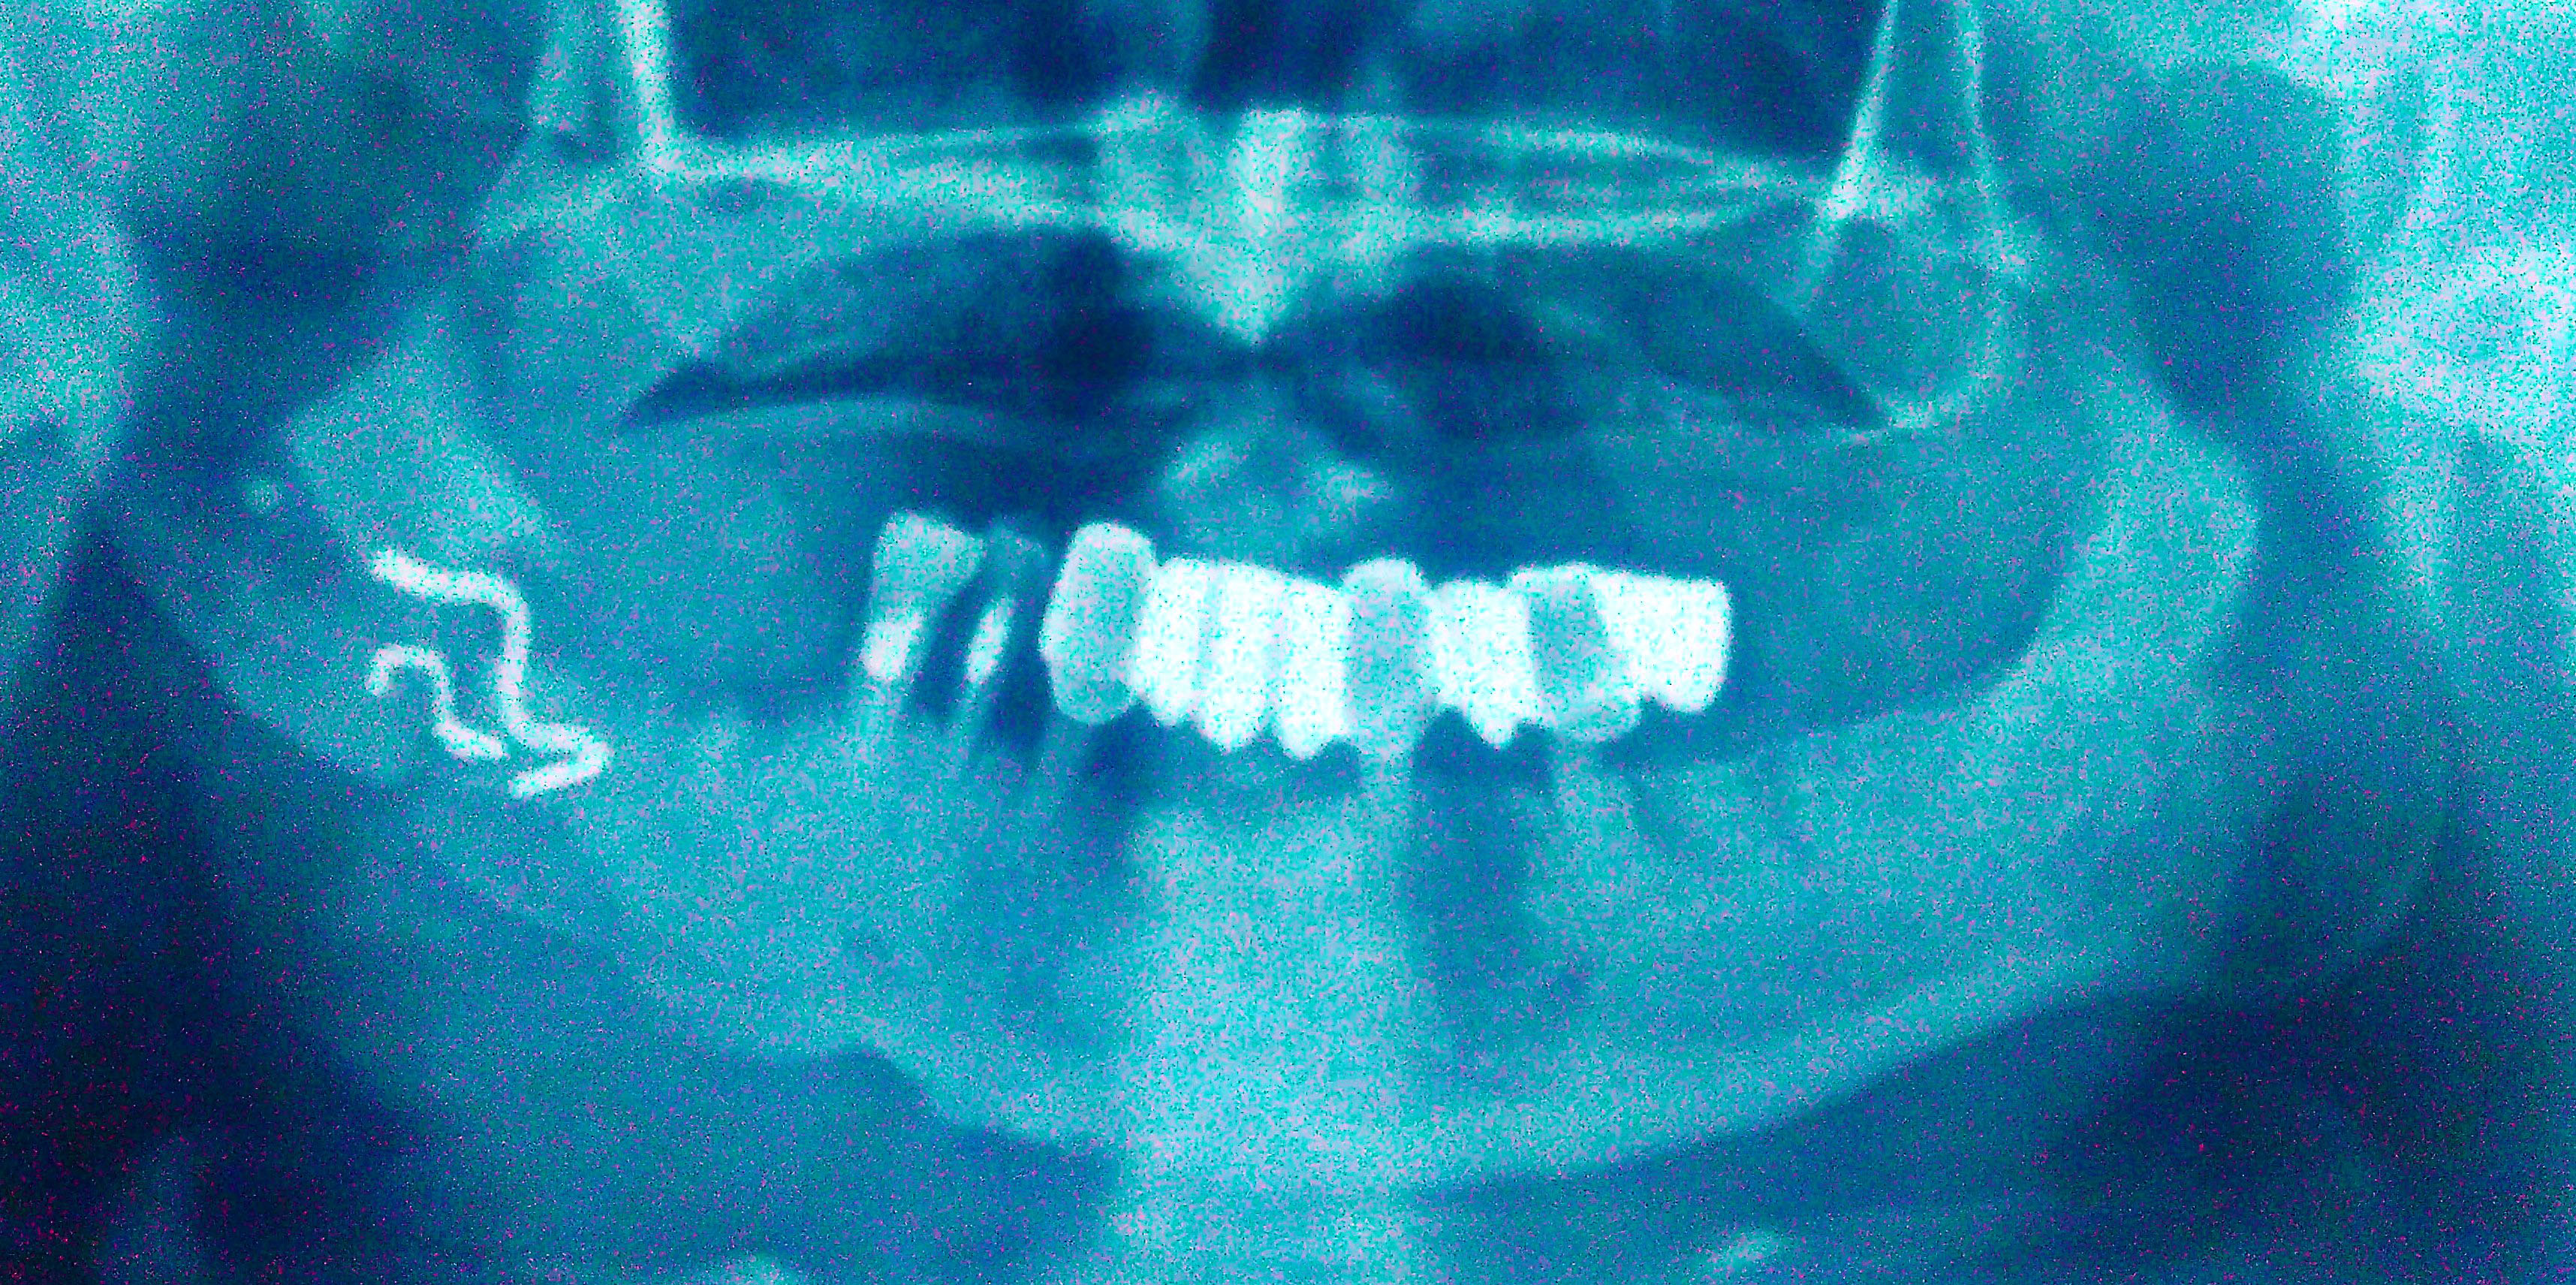

Рентгеновские снимки посттравматического остеомиелита челюсти: Медицинские случаи

Раздел: Образы вокруг